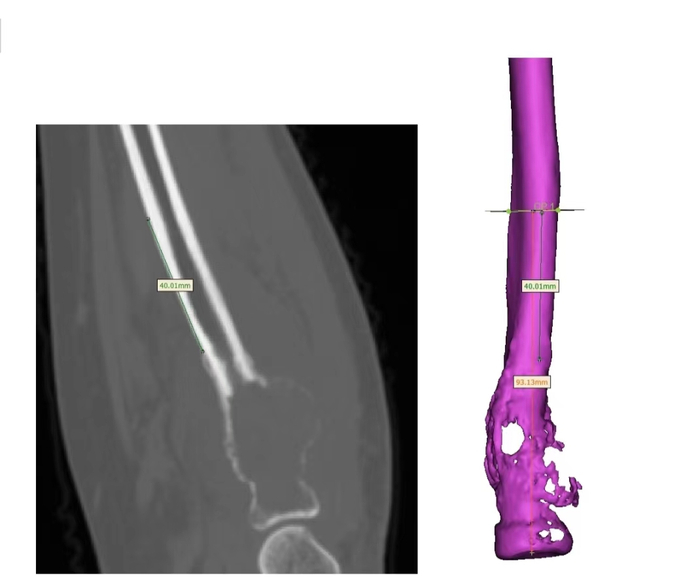

术前假体定制

根据患者CT数据逆向生成骨骼模型

根据患者CT数据逆向生成骨骼模型依据临床医师要求,距病灶远端4mm截骨

假体根据截骨部分进行仿形设计,桡骨关节面为聚乙烯材料,并设置缝合孔,远端设计髓针嵌入剩余骨质,接触面为骨小梁结构,髓针长度50mm,根部直径5mm,末端直径4mm,髓针设计为水泥髓针